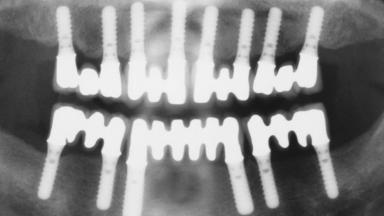

Immediate Loading of Eight Implants in the Maxilla and Six Implants in the Mandible and Final Restoration with Three-Unit and Four-Unit FDPs

# of Implants 14

Type of Implants One-Piece

Prosthesis Type FDP